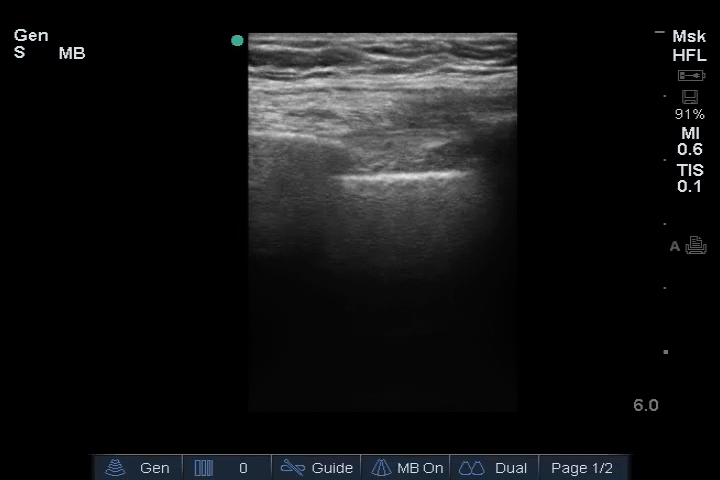

02_Lung_Ant_Left – Normal

Lung: Normal appearance, no B-lines or pleural effusion.